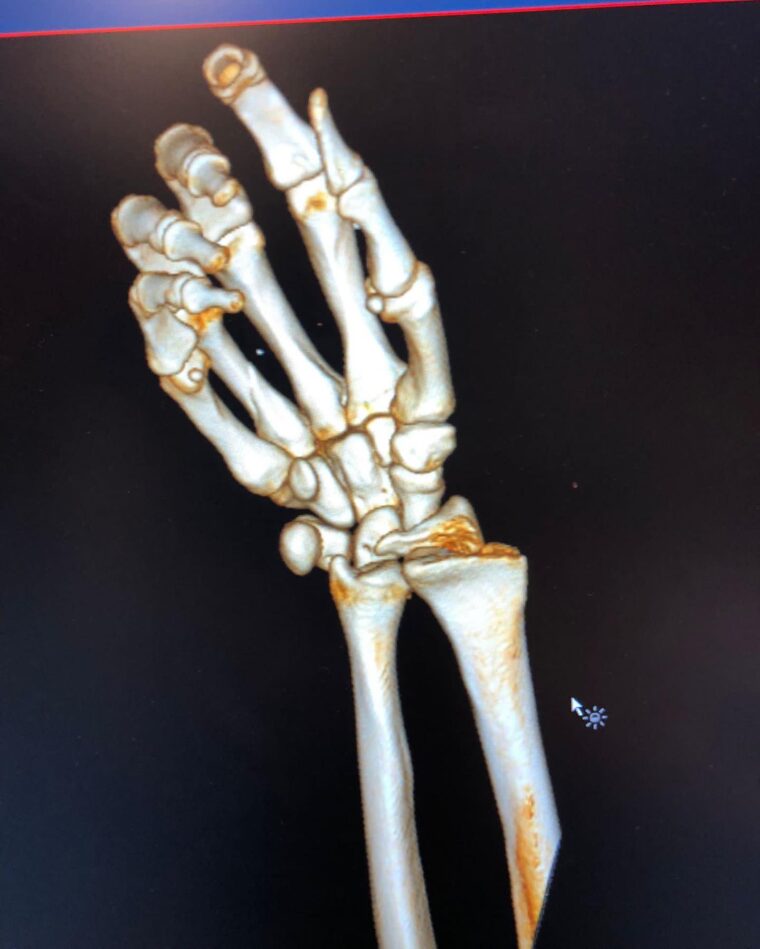

El propio Dovizioso compartió las imágenes en sus redes sociales, en las que mostraba la magnitud de la lesión y las radiografías de la muñeca completamente destrozada. El italiano tuvo que ser operado de urgencia para corregir la fractura, pero ya se recupera con vistas a retomar su actividad lo antes posible.

Aquí tienes todas las imágenes de una lesión que pone los pelos de punta: